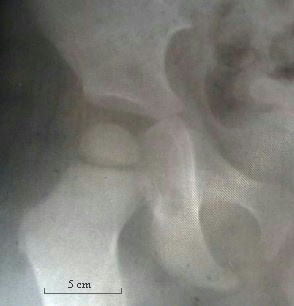

5- articulation : Cette radiographie de hanche montre que l'emboitement du fémur et des os du bassin :

radiographie collège Jules Renard 53000 Laval

ne permet aucun mouvement permet une rotation totale du membre inférieur ne permet pas à ce bébé de marcher